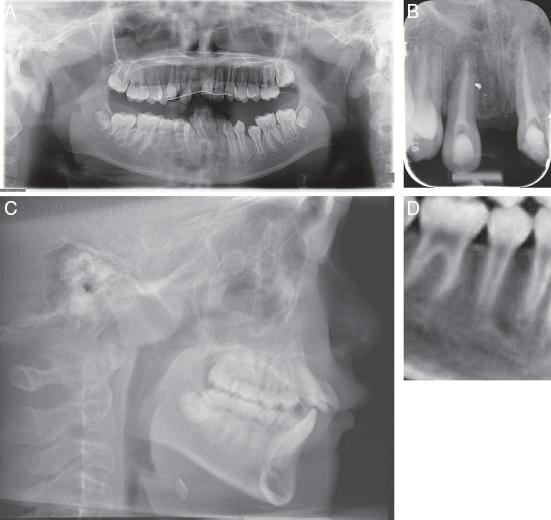

(A) Pretreatment panoramic radiograph. (B) Periapical radiograph showing decoronated #11 and crown attached; Resorption on the apical surfaces of #12 and #21. (C) Lateral cephalogram. (D) CBCT section showing developing tooth #35 with ⅔ root length and (E) Developing tooth #45 with ¾ root length.